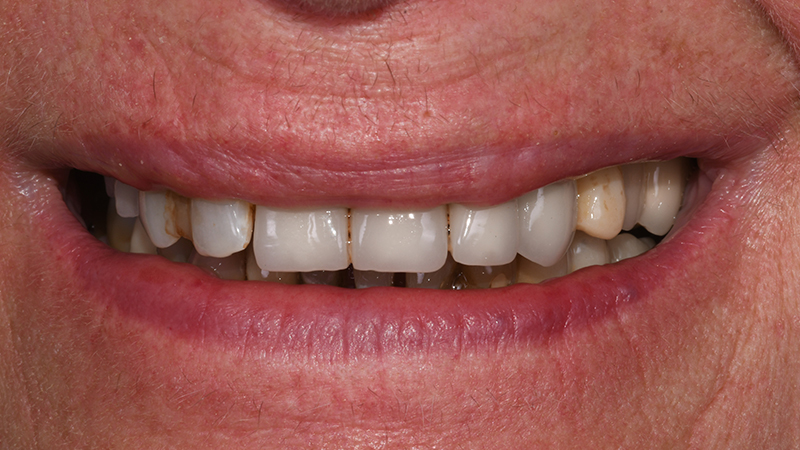

Ponendo vincoli relativamente alle tempistiche e richiedendo una riabilitazione protesica fissa, il piano di trattamento individuale è stato orientato verso riabilitazione protesica fissa a supporto impiantare a carico immediato per la sostituzione degli elementi 13-12-11-21-22-23-24 (Figs. 1, 2).

Fig. 1 - Sorriso in visione frontale extra-orale

Fig. 16 - Sorriso in visione frontale extra-orale dopo applicazione di protesi provvisoria a carico immediato